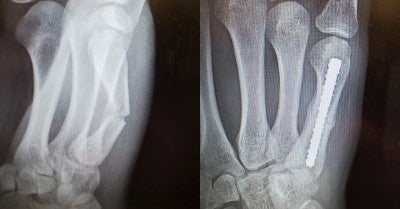

An X-ray done at an outpatient center in Quakertown showed a fracture in his right hand. Mancini was told he would likely need surgery and six to eight weeks of healing.